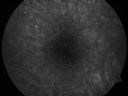

Pigmented Maculae - Mother and Daughter - Normal Visual Acuity503 viewsMothers macular photos     (0 votes)

Pigmented Maculae - Mother and Daughter - Normal Visual Acuity545 viewsMothers macular photos     (0 votes)

Pigmented Maculae - Mother and Daughter - Normal Visual Acuity565 viewsMothers macular photos     (0 votes)

Pigmented Maculae - Mother and Daughter - Normal Visual Acuity646 viewsMothers macular photos     (0 votes)

I checked the mother’s eyes and they look exactly the same.